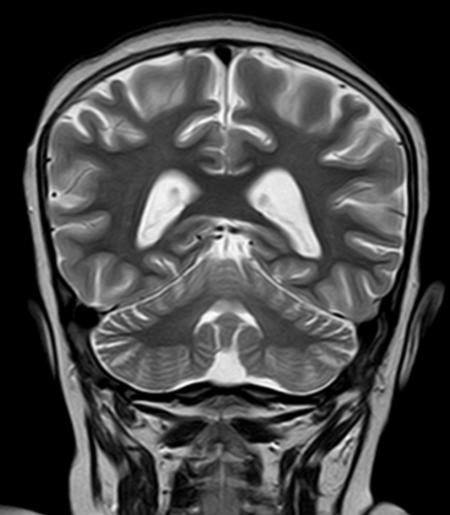

¿Cómo interpreta las imágenes de RM craneal?: